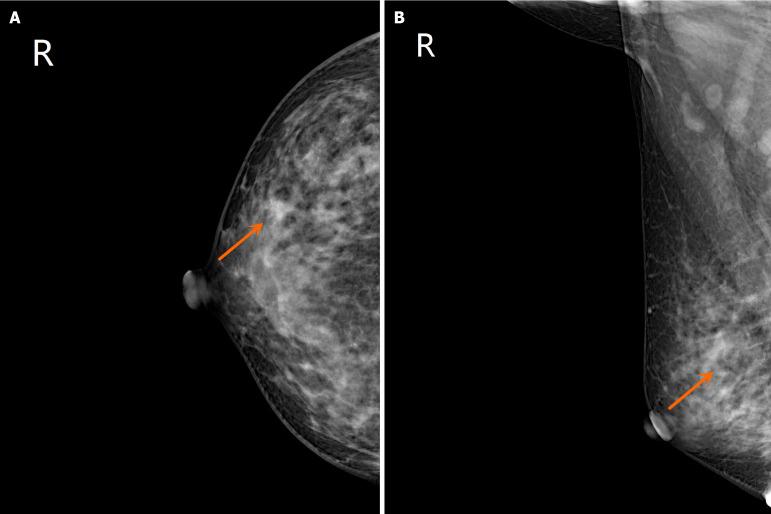

Breast cancer and rectal cancer associated with Lynch syndrome: A case report.

This paper presents a comprehensive review of clinical diagnosis and treatment data from a patient with LS-associated BC and rectal cancer. Moreover, screening data and management guidelines, as well as relevant literature on LS, are included in this report. This study summarizes the molecular pathogenesis, clinicopathological features, and screening and management protocols for LS-associated BC and rectal cancer.